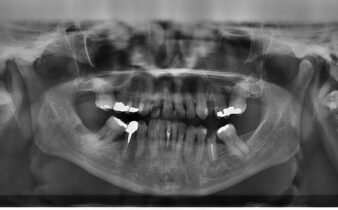

Ortopan

Slikanje zob, oziroma ortopan je potreben, pred določenimi posegi v zobozdravstvu. Na podlagi slike vam zobozdravnik oceni stanje zob, zgornje in spodnje čeljusti, ter zobnih korenin in celo zobno strukturo. Ponavadi vam izdelajo ortopan pred ruvanjem modrostnega zoba, ali pred …